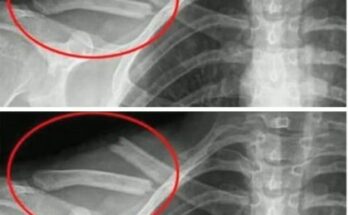

MedlinePlus says it happens when nerves or blood vessels below the neck get compressed. The squeeze develops between the collarbone and the first rib. NHS says it usually affects 1 arm and hand, which helps distinguish it from broader nerve disease. People may notice pins and needles, weakness, tiredness, pain, swelling, or a cold hand. Some also see color changes after carrying bags or lifting objects overhead. That position trigger is one of the most useful clues. Symptoms often worsen when the arm stays raised, stretched, or loaded for too long. A heavy backpack strap, repeated painting, or prolonged shelf work can aggravate the outlet. The discomfort may begin near the shoulder or neck, then travel toward the fingers.

That wider route often points above the wrist. The NHS also notes that symptoms can wake people at night. That overlap can confuse the picture because wrist entrapment can do the same. However, thoracic outlet syndrome often brings arm fatigue, shoulder discomfort, or swelling into the story. MedlinePlus lists weak grip among the common features, which can make ordinary tasks harder. Opening jars, carrying groceries, and holding the phone may all become more irritating. Some people have a cervical rib or a tight fibrous band that narrows the space further. Others develop muscle crowding or posture-related compression after repetitive work or injury. The hand then becomes the messenger, while the real bottleneck sits closer to the chest. Doctors usually sort this out by looking at mechanics and associated signs.